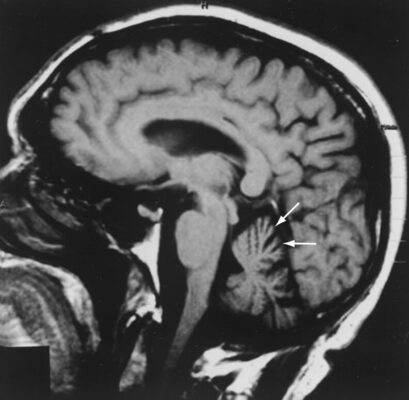

Chẩn đoán ban đầu về chứng thoái hóa tiểu não gai được nghi ngờ bằng cách khởi phát các triệu chứng ở người lớn. Chụp MRI hoặc CT não có thể phát hiện teo tiểu não và nhiều cấu trúc dưới vỏ não khác (Hình 5–1). Xét nghiệm di truyền phân tử để xác định gen có mở rộng lặp lại trinucleotide có thể hữu ích trong việc nhanh chóng xác định những người mang gen khác trong gia đình. Nhiều rối loạn trong số này hiện có thể được xác nhận bằng xét nghiệm DNA. Các đặc điểm lâm sàng của các rối loạn này được liệt kê trong bảng đi kèm (xem Bảng 5–1).